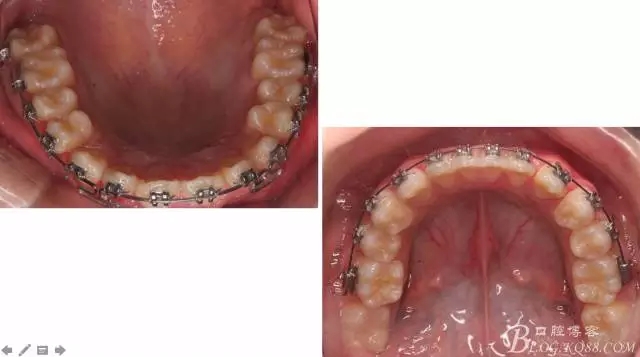

佩戴三個月的FR2, 效果奇佳!前牙基本達到淺覆蓋,淺覆合!接下來進入二期直絲弓固定正畸,排齊階段!

下頜配合多曲方絲,三角牽引,調(diào)整咬合。